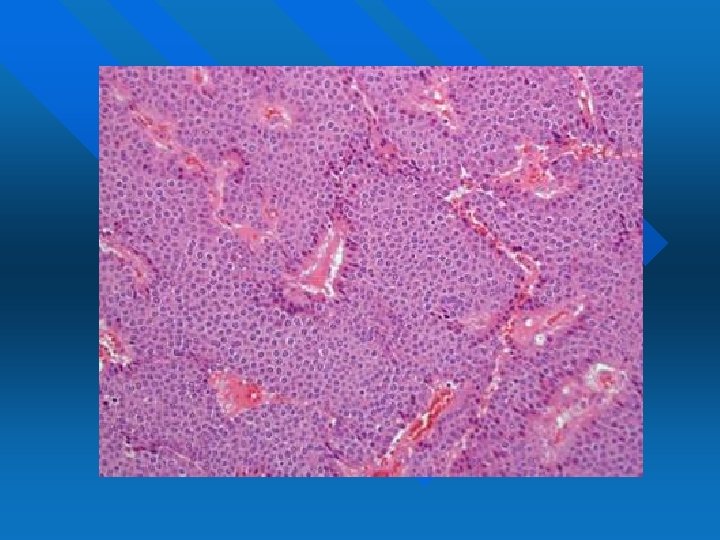

NEOPLASIE DEL PICCOLO INTESTINO Sono prevalentemente carcinoidi (tumori neuroendocrini ben differenziati) n A crescita sottomucosa n Pattern di crescita insulare, circoscritta n Cellule piccole, monomorfe, con nucleo tondo e citoplasma finemente granulare n